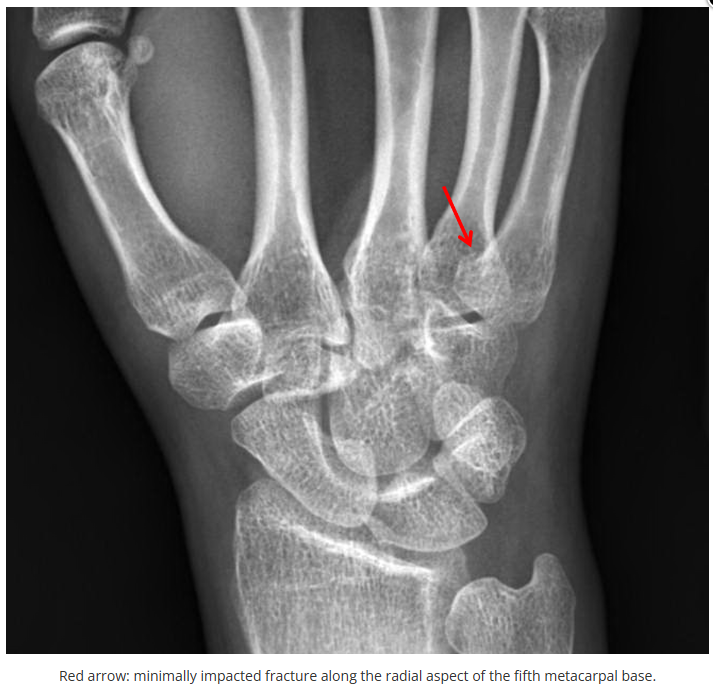

这些腕与手的骨折X线片如果没有标注箭头,你还能识别出来吗?

X线读片是骨科医生的基本功。

今天是腕部与手的X线片。所有X线片都

带有标注和说明

,可以选择长按图片,

自动翻译相关说明

。